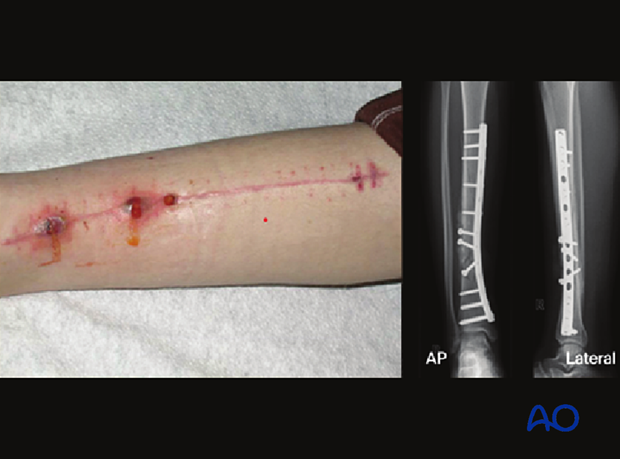

The patient developed severe deep infection at six weeks postoperative.

At the second treatment the plate was removed, and the fracture site was debrided. A two-fixation block ring system was applied.